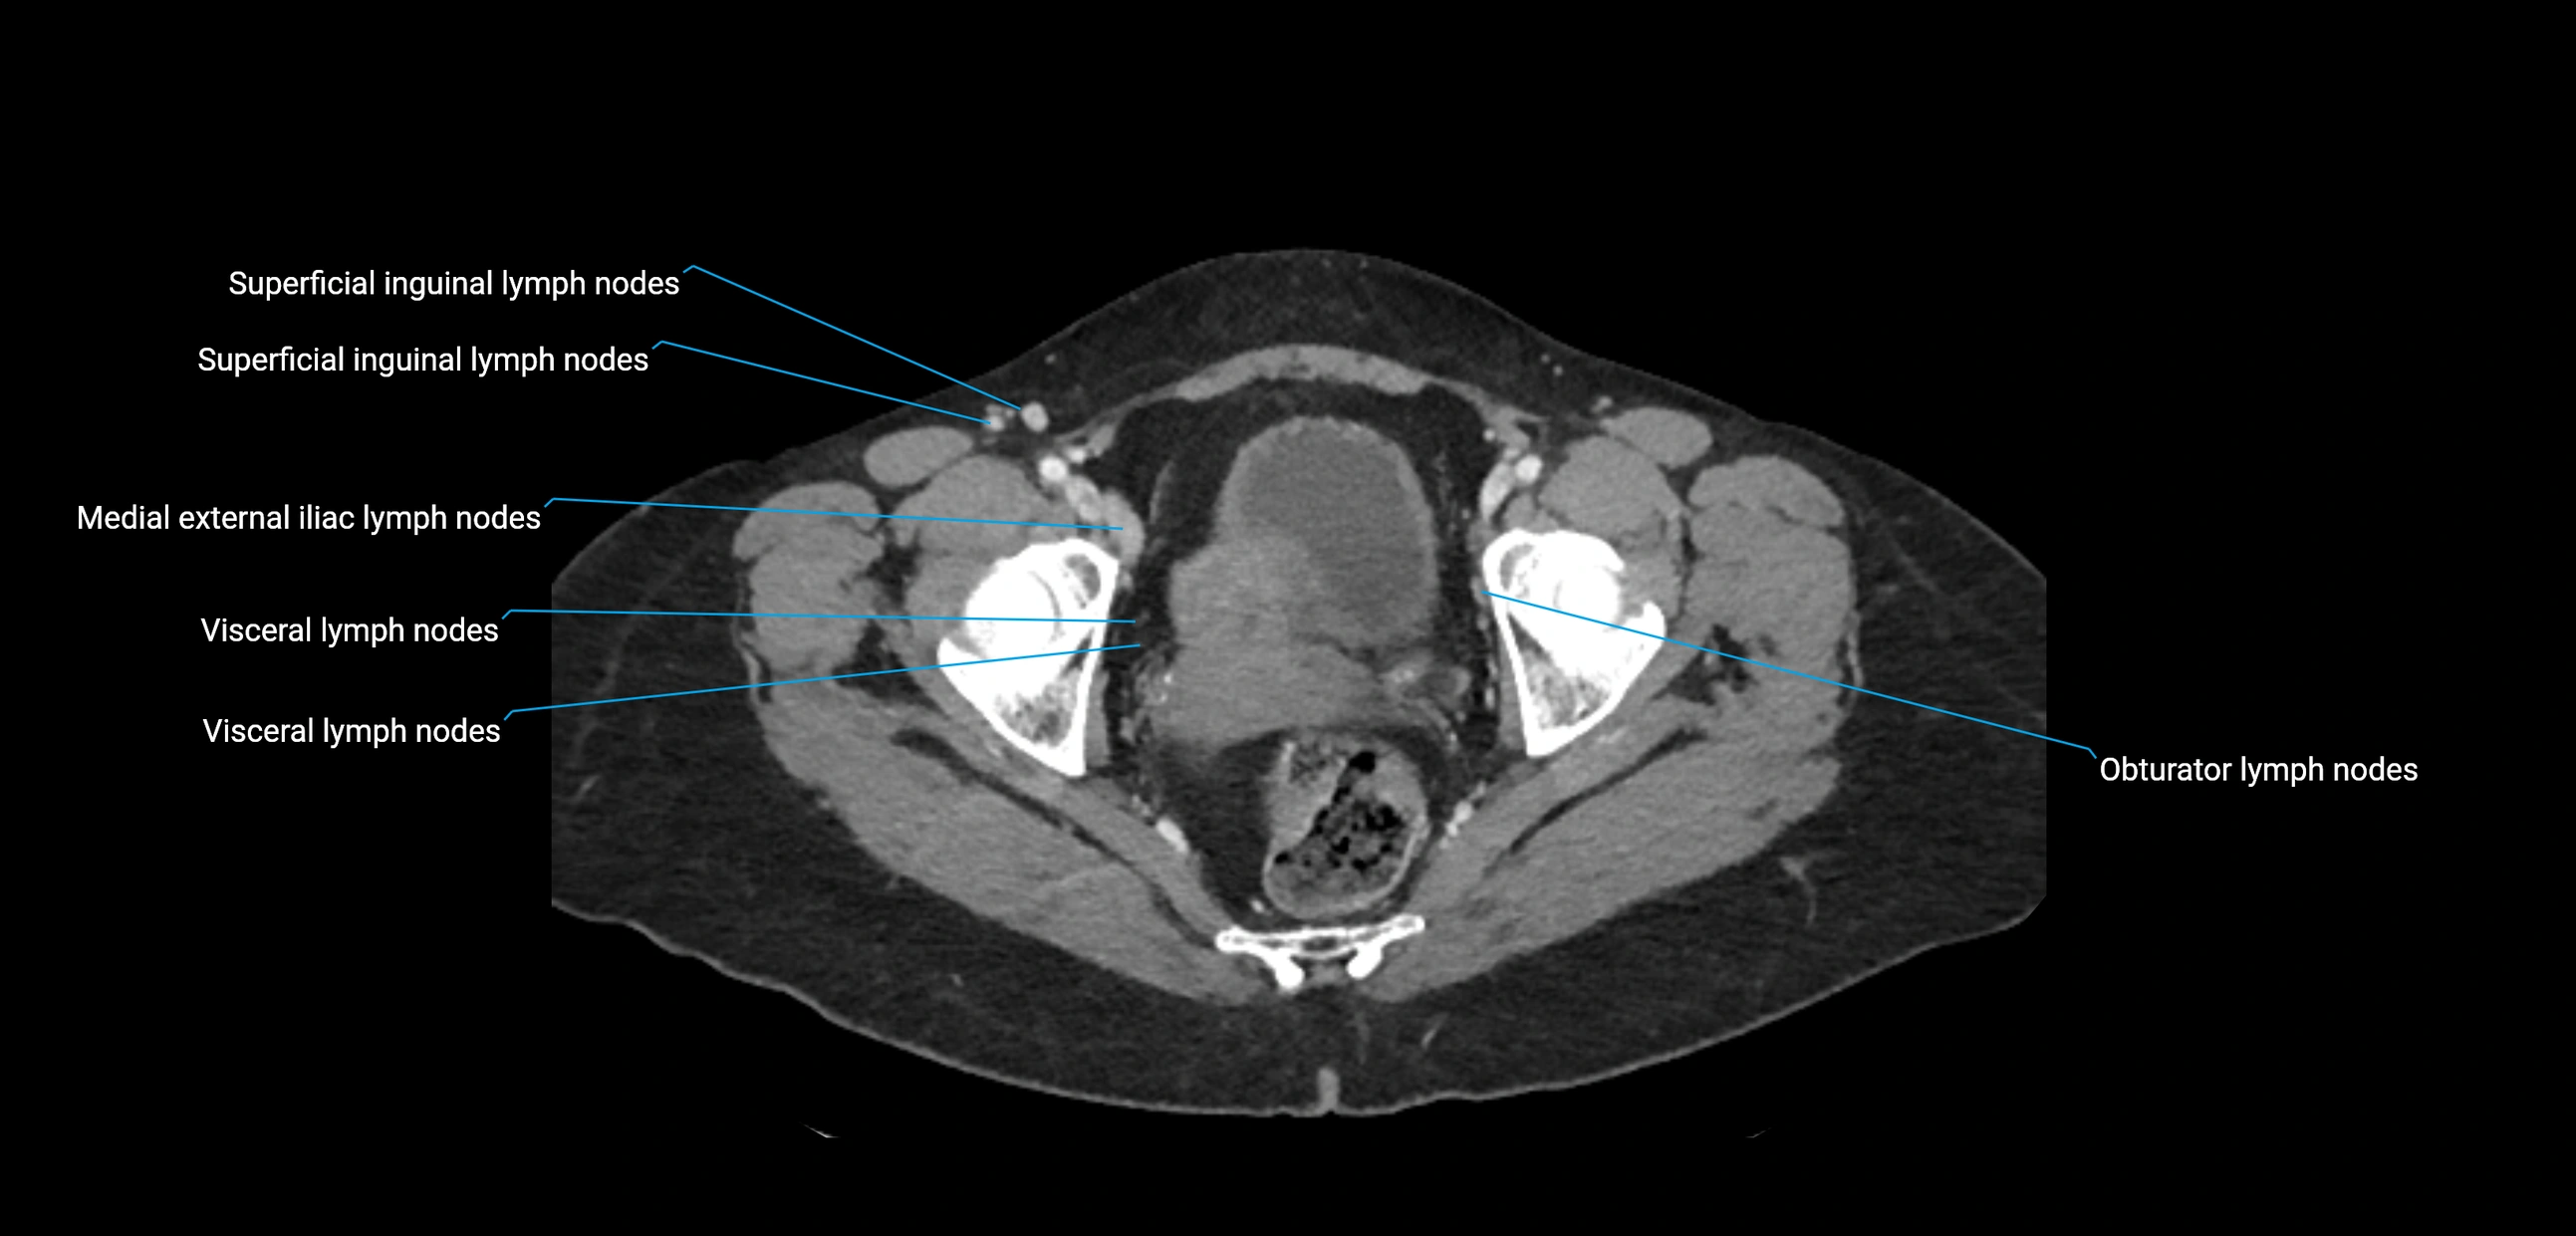

CT image

image